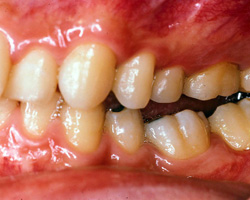

今回、この患者様のスプリント調整は、装着時から三回までは一週間ごと、四回から七回までは三週間ことのを三カ月かけて調整。その後、スプリントを再製作し装着、以降三カ月に一度の調整を二年間線り返しました。写真3) 4) 5) 6)はその時の状態です。臼歯部が大きく離閉じているのがおわかりかと思いますが、この隙間が頭蓋骨の歪み、頚椎の歪みが咬合面上に現れた状態で、決して歯牙が歯槽骨内に埋入したわけではありません。

| 写真5)2年後の状態(左側) | 写真6)スプリントをはずした時の状態(左側) |

写真7) 8) 9) 10)は街前の姿勢と術後の姿勢です。頭位姿勢を意識したときに下顎の安静位から対咬する歯が接触するまでの時間は短いわけですが、しかしながら、どのような状態で歯牙が接触を行うか?また終了するか? このことが生体に大きく影響を与えるのです。

(患者様のメモ)顎関節蒲、肩こり、頭痛、腰痛、右足後部の摘みがなくなり集中力がついた。風邪もひかなくなり、ひいても高熱がでなくなった。